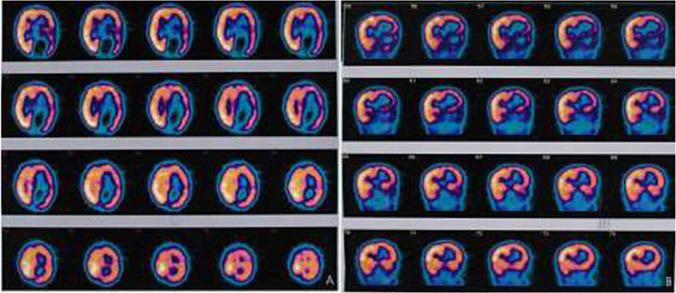

We report an unusual case of hemimegalencephaly (HMG) associated with ipsilateral congenital-infiltrating lipomatosis of the face in a five-month-old boy. Hemimegalencephaly is a rare but unique malformation characterized by enlargement of all or parts of a cerebral hemisphere. The affected hemisphere may have focal or diffuse neuronal migration defects, with areas of polymicrogyria, pachygyria and heterotopia. Our aim was to investigate morphologic abnormalities occurring on the affected hemisphere by Magnetic Resonance Imaging (MRI), but some MRI findings were also noted outside of the affected hemicerebrum. There are a few case reports that have described various other abnormalities accompanying this condition, such as enlargement of ipsilateral brainstem, cerebellum and left lateral ventricle. MRI may be the most useful method demonstrating features of hemimegalencephaly with infiltrating lipomatosis of the face. However, studies using electroencephalogram (EEG) and brain single photon emission computerized tomography (SPECT) can show distinct variants of discharges and brain-perfusion anomalies.

我们报告了一例罕见病例,一名五个月大的男婴患有半侧巨脑症(HMG),并伴有同侧面部先天性浸润性脂肪瘤病。半侧巨脑症是一种罕见但独特的畸形,其特征是大脑半球的全部或部分增大。受影响的半球可能有局灶性或弥漫性神经元迁移缺陷,伴有多小脑回、巨脑回和异位症区域。我们的目的是通过磁共振成像(MRI)研究受影响半球出现的形态学异常,但在受影响的大脑半球之外也发现了一些MRI表现。有一些病例报告描述了伴随这种情况的各种其他异常,如同侧脑干、小脑和左侧脑室增大。MRI可能是显示半侧巨脑症伴面部浸润性脂肪瘤病特征的最有用方法。然而,使用脑电图(EEG)和脑单光子发射计算机断层扫描(SPECT)的研究可以显示放电和脑灌注异常的不同变体。